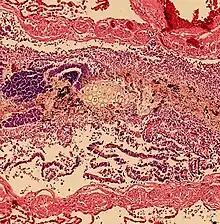

Aspiration pneumonia is when bacteria is carried into the respiratory tract via aspiration and subsequently causes an infection of the lung. Any substance or object that is aspirated into the airway has the potential of carrying infectious agents with it into the respiratory tract. It primarily affects older adults and can be especially severe in patients with learning disabilities, or disorders of abnormal swallowing.[14]

Aspiration Pneumonitis

Aspiration pneumonitis (Mendelson's syndrome) is chemical injury of lung tissue secondary to aspiration of regurtitated gastric acid.[15] The syndrome was first described among pregnant patients[16] after the administration of anesthesia, though it can occur in any scenario where gastric contents are aspirated.[17]